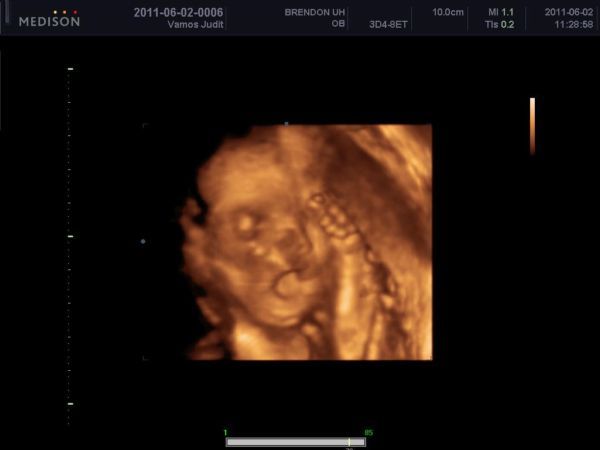

4D, mi voltunk a 16. héten ugye, az nagyon jó volt

csak kicsit hosszú, 30 perc... (élveztem, csak a hasam keményedett be...) elvileg a 25. héten megyünk újra, meg a 30. hetit is 4D-ben kértük... nagyon rossz, a barátnőknek mindig átkapcsol a doki pár percre 4D-be a sima vizsgálatnál, nekünk soha, pedig az a gép is tudná